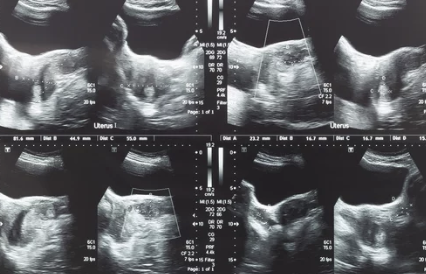

2. 자궁근종 수술 후 재발할 수 있는 가능성이 있으므로, 정기적인 검진과 주기적인 진료를 받는 것이 중요합니다.

3. 수술 전에 자궁근종의 크기와 증상에 따라 수술의 유무를 결정하는 것이 중요합니다. 근종이 크거나 증상이 심한 경우에는 수술을 고려해야 합니다.